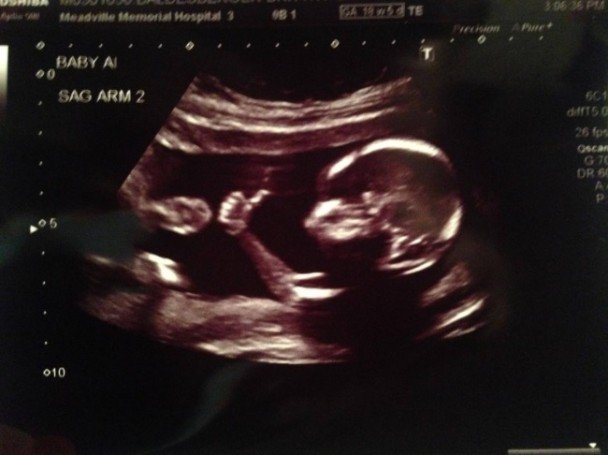

令人震惊的画画:胎儿腹中竖拇指(图)

外国一名网民早前上载一怀孕妻子的超声波照片,尚在腹中双胞胎的其一名婴儿,竟“懂得”竖起拇指,像说在母腹内一切很好。